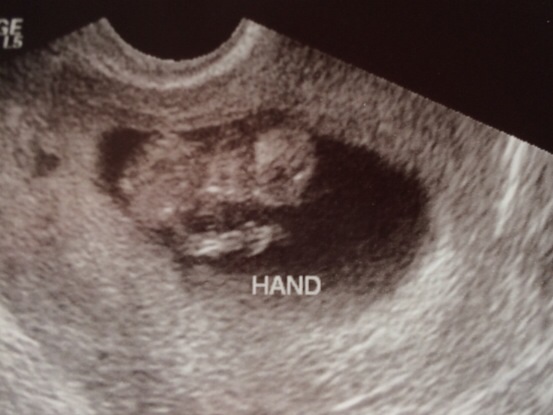

Well ladies I think it's safe to say baby has made a happy home for 7-8 more months. I will be 11 weeks tomorrow. So excited to say baby looks awesome! He/she is was waving at me and dancing all over the place. I got to see a straight spin along with hands and feet. He/she so far looks to have long legs like mommy.

Baby also had a heartbeat of 163 and measuring right on track. I go back in on May 20th which seems so far away! But 3-4 weeks after that we get to go in for a early anatomy scan to make sure baby is developing right and of course find out what we are having.